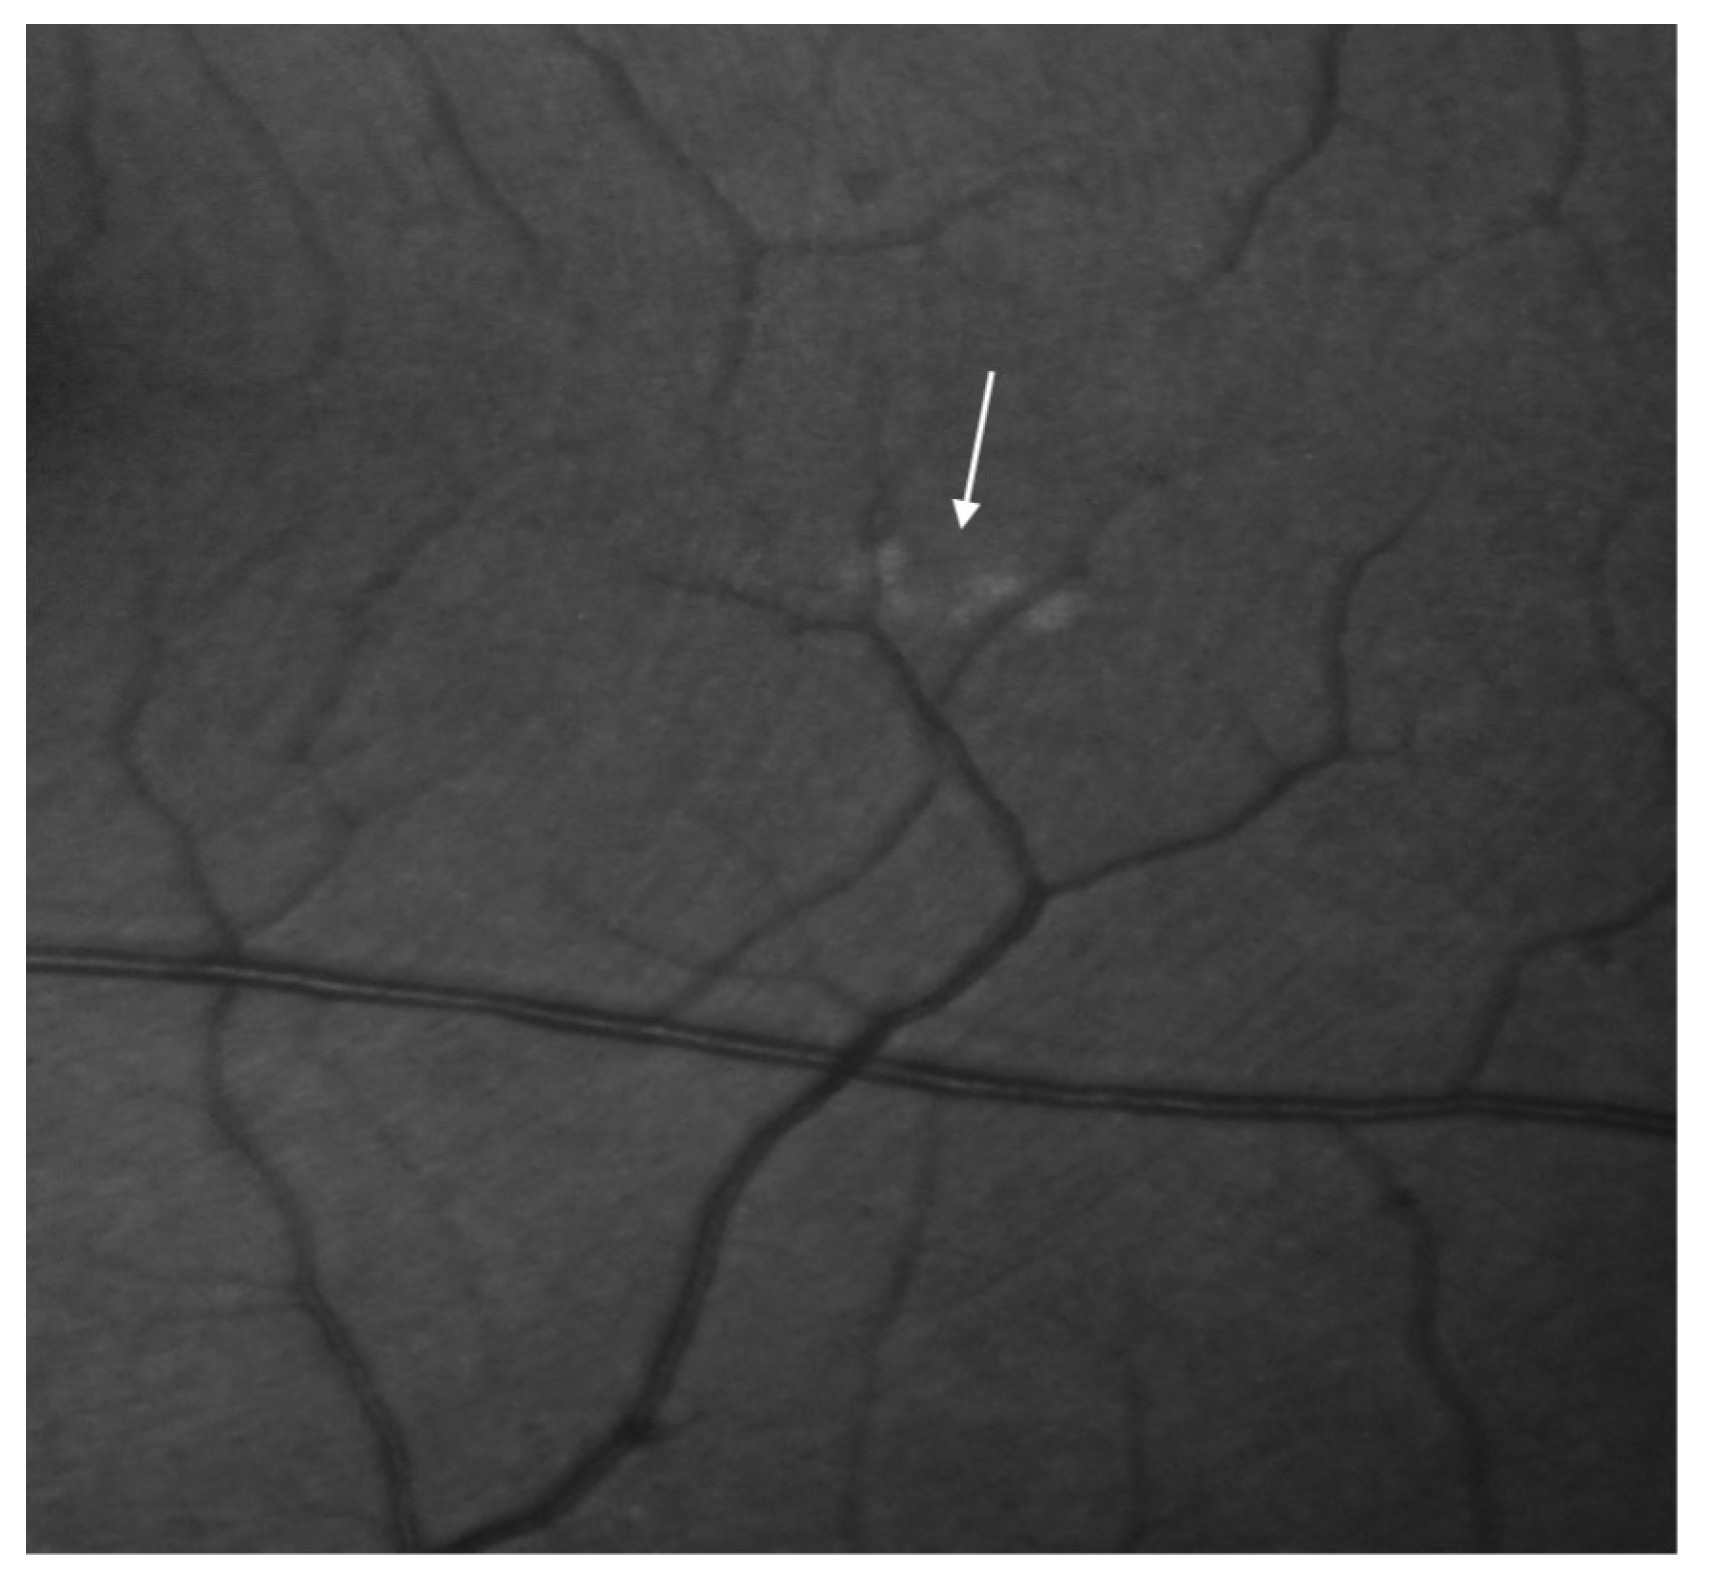

Figure 4.

Fluorescein angiography of the right and the left eye. Discrete retinal lesions in the left eye (the arrow demonstrates focal drusen).

The retinal drusen were observed in the retina of the left eye (Figure 5).

Figure 5.

Focal drusen around the subretinal region of the left eye demonstrated in the fluorescein angiography (the arrow demonstrates focal drusen).

Late-phase indocyanine green angiography (ICGA) also confirmed the presence of lesions, demonstrated by the small, linear, focal hyperfluorescence of the lower part of the central fovea exclusively in the left eye. It is not certain whether these changes are the result of focal RPE atrophic lesions.